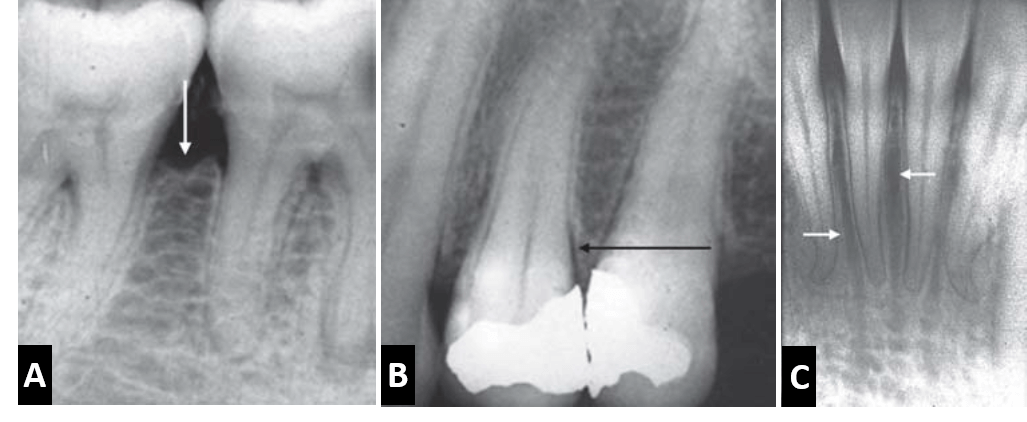

La pérdida ósea atribuida a la enfermedad periodontal puede ser estimada como la diferencia entre la altura ósea fisiológica y la altura de hueso remanente. Cuando está perdida ósea ocurre en áreas aisladas abarcando menos del 30% del hueso de soporte es llamada perdida ósea localizada; mientras que cuando el compromiso óseo se presenta en ambas arcadas dentarias de forma general tanto en la arcada superior como en la inferior con más del 30% de compromiso del hueso de soporte es descrito como una pérdida ósea generalizada. Así también, cuando la pérdida ósea forma un ángulo con un plano imaginario entre la unión cementoadamantina de dos dientes adyacentes, es conocida como reabsorción ósea de tipo vertical o angular; y cuando la perdida ósea se observa de forma paralela con el plano imaginario entre la unión cementoadamantina de dos dientes adyacentes, se conoce como reabsorción ósea de tipo horizontal.

Por otro lado, la extensión de un bolsillo periodontal entre las raíces de un diente multirradicular conllevara al compromiso de la furcación, la cual podrá observarse por medio de una radiografía cuando la reabsorción ósea cuando esta se extienda en sentido apical, mas allá de la furcación. El compromiso óseo de la furcación de una molar mandibular es posible observarla con mayor claridad, a diferencia de un molar superior donde la raíz palatina se superpone sobre la furcación.

Entre los factores predisponentes de enfermedad periodontal observables radiográficamente, se pueden observar irritantes locales como los cálculos o las restauraciones defectuosas. Los cálculos dentales corresponden a placa bacteriana acumulada y calcificada, las cuales se pueden observar como espículas irregulares radiopacas a nivel cervical por mesial o por distal; o pueden ser observadas también rodeando un diente en su zona cervical como un anillo radiopaco, sin embargo, pequeños depósitos de cálculos pueden pasar desapercibidos en una radiografía.